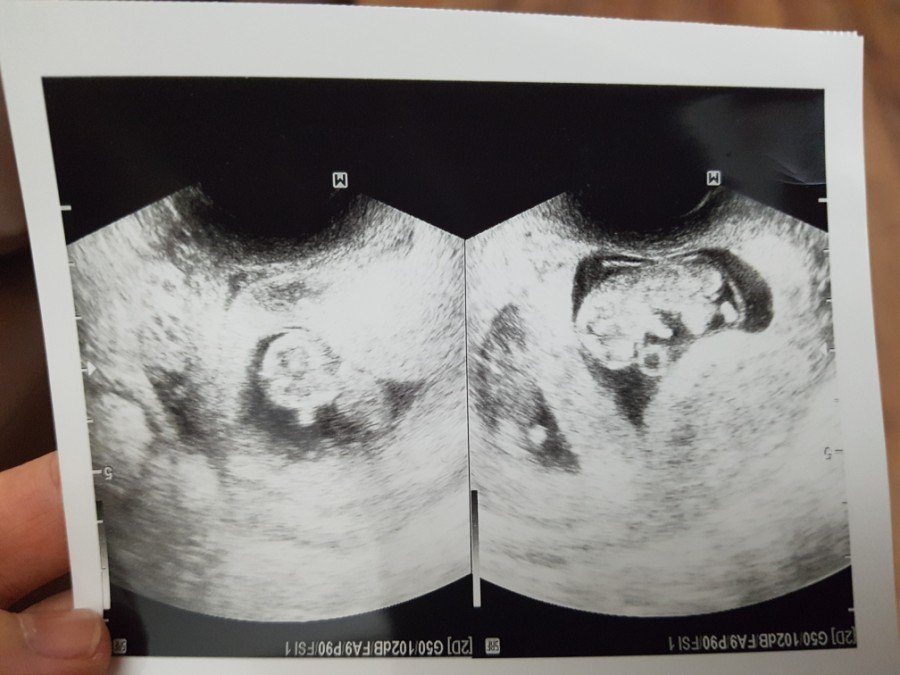

얼렁뚱땅 배아시절

1522237558140.jpg

누가 일렁이고 누가 뚱땅 일꼬_

너희들 초초초마이크로미니미 사진이다.

주변에 물어보거라.

이런 사진 갖고 있는 엄마아빠

흔치 않다.

얼렁뚱땅 너희들은 이렇게 특별하단다.

젤리곰시절

1522280281248.jpg

콧구멍 속에 젤리곰 등장.

너희들의 등장을 얼마나 기다렸다 규.

걱정 어린 기다림이 무색하게도

보란 듯이 심장도 반짝반짝 빛났고

씩씩하게 심장도 뛰었단다.

고마워, 젤리곰.